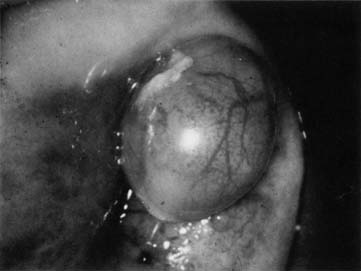

ENDOMETRIOSIS

Cervical endometriosis (Fig. 7) can mimic multiple lesions, including gestational trophoblastic disease (GTD), because of its high-vascular nature. History and physical examination to evaluate the likely nature of the lesion, including a laboratory assessment of human chorionic gonadotropin are all prudent before consideration for biopsy or treatment. Biopsy of areas of trophoblastic disease are generally avoided, because the invasive neovascularization that accompanies these lesions may lead to significant hemorrhaged, unlike endometriotic implants that are less likely to have postbiopsy hemorrhage. Symptoms from a cervical lesion are generally related to bleeding or discharge and pelvic pain is more likely referred from endometriotic implants elsewhere in the pelvis. These areas should respond to general therapy for endometriosis (the use of Lupron, for example) and failure to respond should lead to biopsy to assure that this is the diagnosis if not performed previously.

Fig. 7. Cervical endometriosis.